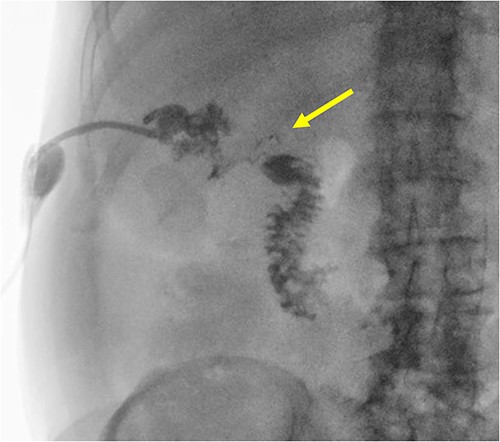

The patient is a 72-year-old male who underwent laparoscopic cholecystectomy for gangrenous cholecystitis at an outside hospital 23 months prior to our initial visit. Other pertinent medical history included ischemic stroke with resultant speech/vision deficits and left-sided hemiparesis, bladder cancer, testicular cancer, and colon cancer. His surgery was complicated by recurrent liver abscesses diagnosed 7 months postoperatively. He was treated with antibiotics and underwent multiple image-guided percutaneous drainages in the 9 months after his index operation. Unfortunately, many failed intravenous and oral courses of broad-spectrum antibiotics had resulted in treatment resistant Clostridium difficile infection, requiring stool transplant for successful eradication of his colonic infection. He presented to the emergency department 1 day after a drain placement procedure with complaints of right upper quadrant abdominal pain, nausea, and emesis. Similar to the first case presented in this report, the oral contrast administered during prior abdominal CT scan was unable to demonstrate this fistulous connection. Fistulogram performed through the abdominal drains demonstrated a fistulous connection between the abscesses and the gastric antrum (Fig. 4). Additionally, two small cutaneous fistulae in the right abdominal wall were identified, draining the overflow purulence from the perihepatic abscess cavities through the skin. He underwent endoscopic closure of the gastro-perihepatic fistula using the over-the-scope clip, followed by intraoperative abdominal wall fistulae washout 5 days later (Fig. 5). Both fistula cavities were packed with cotton packing strips, and the percutaneously placed drains were removed. He was discharged with oral antibiotics. Repeat CT scans at 1 and 3 months postoperatively demonstrated smaller perihepatic abscesses. Patient reported no symptoms of recurrence of abscesses or fistulae. The abdominal wall fistulae had decreased purulent drainage and continued to be managed with wet-to-dry packing.

A radiographic fistulogram demonstrating the fistulous tract communicating with the proximal duodenum/gastric pylorus.